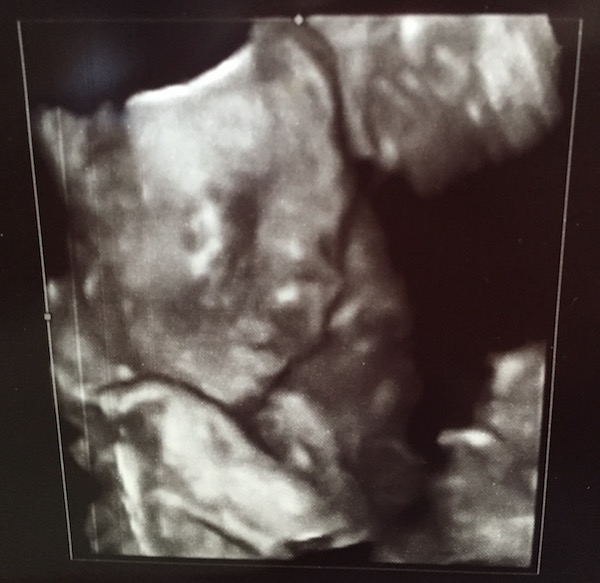

Week 22: Up close and personal

The highlight of this week was without a doubt my second trimester ultrasound. (That’s the big one!) Lee and I got to see some seriously amazing close-ups of our bitty bean. Honestly, I think I was in awe the whole time, complete with my mouth hanging open and whispering “wow” every two minutes. We saw Birdie’s spine, brain, arteries, stomach … even the four chambers of that little heart pumping away. It was incredible to see this small person who really is just that—a miniature human with working parts.